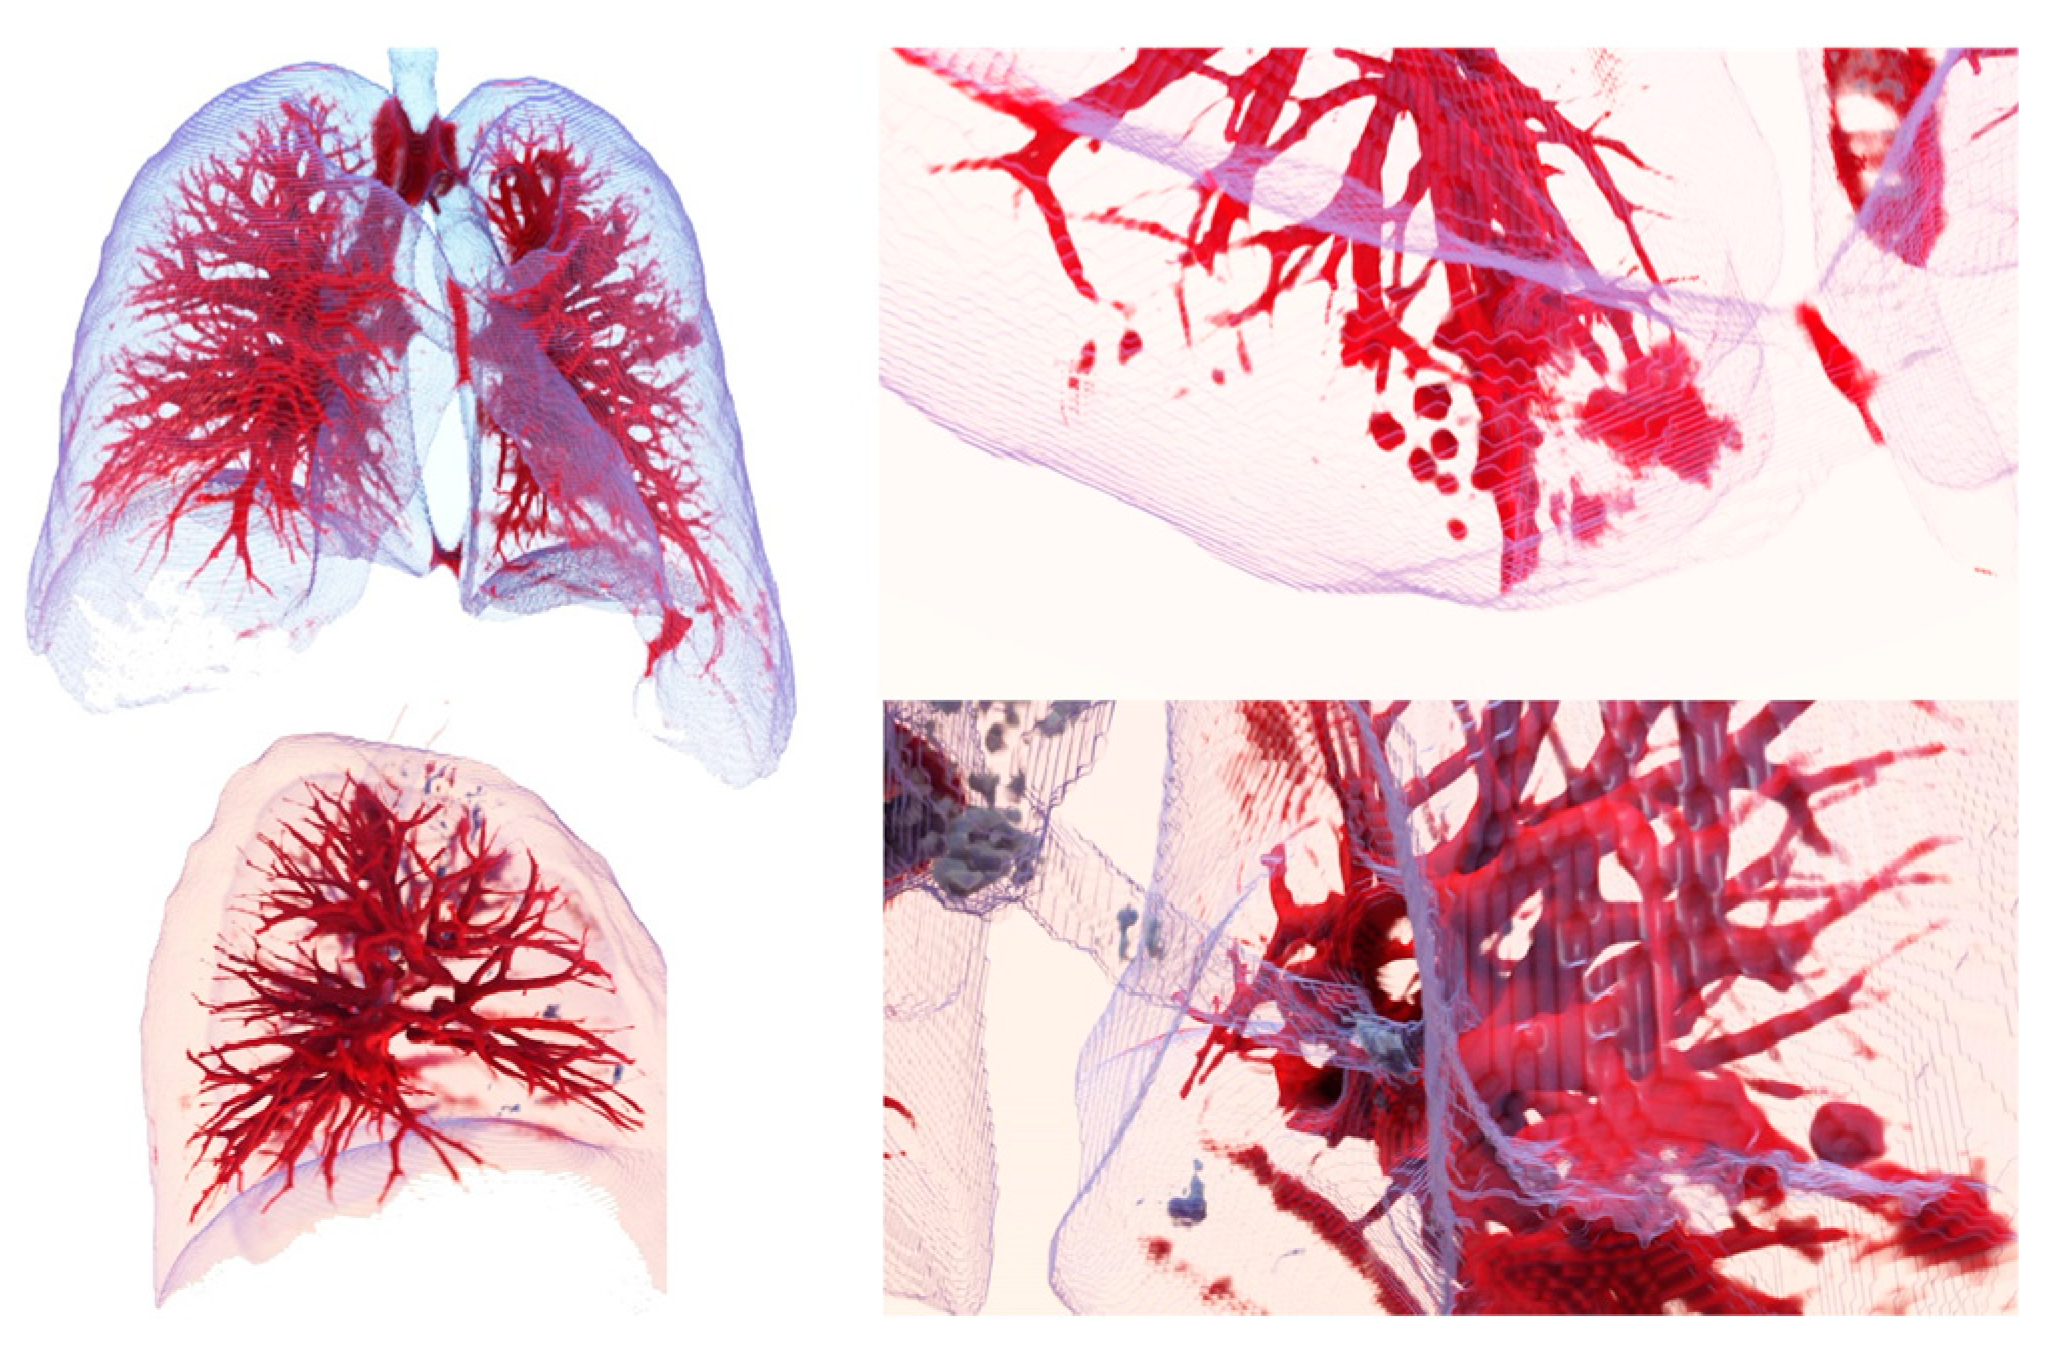

3.1. From dicom to 3D Models with Automatic Segmentation

3.2. Results Visualization